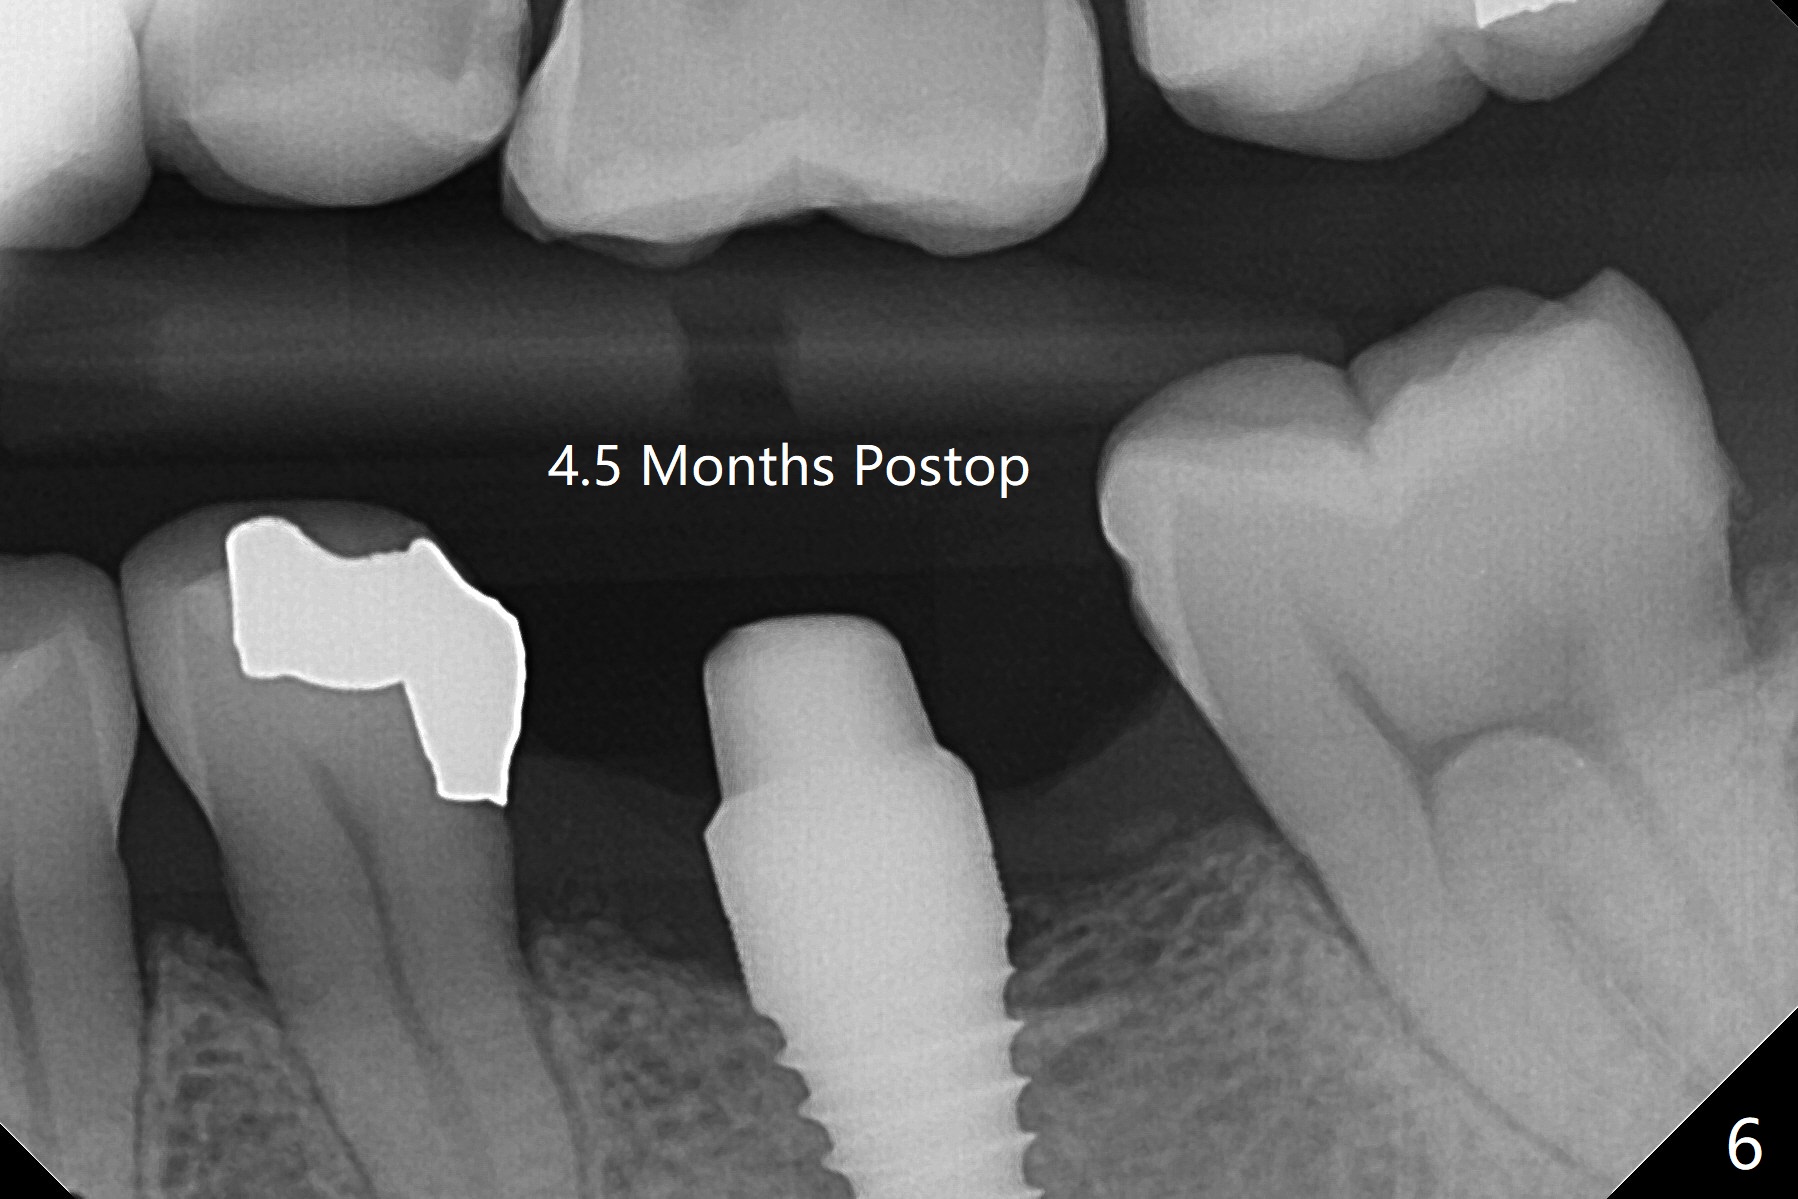

适当更改导板(为两段式接近圆柱状植体设计)钻洞顺序(根尖钻头小,而一段式植体根尖特别尖),5x14毫米一段式软组织水平植体植入,扭力大约35Ncm(图一),略微种深(图二:长箭头)后,磨短基台(与图一对比;左上6伸长),颊侧,远中,舌侧边缘降低(图二,三:<;增加基台高度,提高牙冠固位),制作临时牙冠(图四:P),主要目的将近中牙龈推向近中(图三:空箭头),暴露近中基台边缘,以后好取模。总之,一段式植体需要考虑临时修复。术后两个月临时牙冠和周围牙龈正常(图五)。术后4.5月轻度骨质吸收(图六),临床上看不出来螺纹将要暴露,取模。病人抱怨用临时牙冠咀嚼疼痛,不咬后没有不舒服,其实临时牙冠咬合面穿孔,牙龈正常,永久粘固剂没有外溢(图七)。术后4.5-6个月植体周围骨质吸收(图六,七)。牙槽嵴处钻洞应与植体直径一样才能减少骨质吸收。